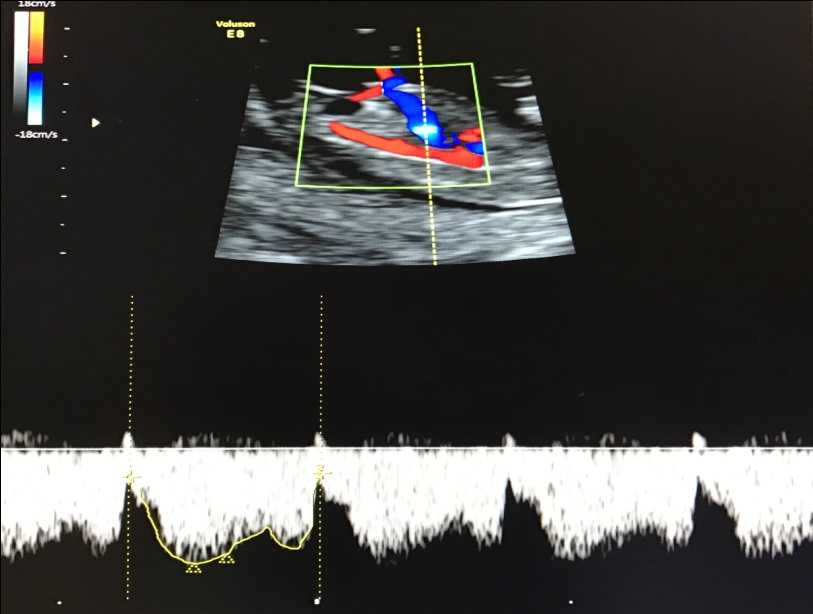

— кровоток в венозном протоке – это маленький сосуд в печени плода. При обратном (ретроградном) токе крови в данном сосуде можно предположить, что у плода хромосомный синдром, либо врожденный порок сердца.

Нормальный кровоток в венозном протоке

Но важно правильно получить этот кровоток и дать ему оценку. Для этого требуются определенные навыки и квалификация врача, которые подтверждаются ежегодной сертификацией FMF.. — кровоток через трикуспидальный клапан в сердце плода